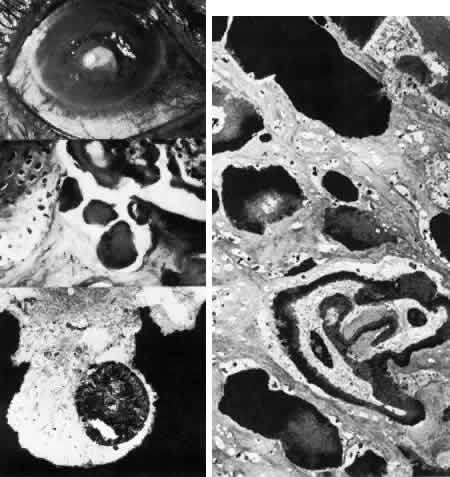

ENDOTHELIAL DYSTROPHIES

Congenital Hereditary Endothelial Dystrophy

Initially described by Maumenee173 in 1960, this congenital disorder of the endothelium is characterized clinically by diffuse, bilaterally symmetric corneal edema (Figs. 5 AND 15; Color Plate 1J). The autosomal recessive variety is present at birth and is relatively stationary. Symptoms of discomfort are not prominent despite profound epithelial and stromal edema. Nystagmus is common.174 A dominantly inherited form is less severe, developing in the first or second year of life, and, in contrast to the recessive variety, progressive photo(text continues on p. 27) phobia and tearing are the initial symptoms. Nystagmus is generally absent.174 As in all instances of congenital corneal clouding, it is important to rule out congenital glaucoma.

Fig. 15. Congenital hereditary endothelial dystrophy. Top left. Clinical photograph of eye of a 14-year-old male with severe form of the dystrophy shows diffuse ground-glass stromal opacification. Top middle. In a mildly affected 20-year-old female, the cornea has moderate diffuse haze and visual acuity is 20/200. Top right. On slit lamp biomicroscopy, diffuse edematous thickening of the corneal stroma is evident in same patient as top middle photograph. Middle right. Light microscopy of a case with uniformly thickened (approximately 35μm) Descemet's membrane (DM) covered posteriorly by extremely attenuated endothelial cells (arrowheads). S, posterior stroma; AC, anterior chamber (hematoxylin-eosin, × 600). Bottom left. Transmission electron micrograph of same case as middle right micrograph reveals anterior portion of Descemet's membrane (DM) to have normal thickness and banded structure. The markedly thickened (approximately 20 μm) posterior layer exhibits both 55 nm and 110 nm banding (circled) interspersed with homogeneous material. En, endothelial cell; AC, anterior chamber; S, posterior stroma (× 9200). Bottom right. At higher magnification, the abnormal posterior zone is seen to consist of multiple laminations of basement membrane-like material (*) and fine filaments. En, endothelial (× 42,000).

The degree of edematous corneal clouding varies from a mild haze to a milky, ground-glass opacification. Epithelial microbullae may be obvious, and stromal thickness may be increased threefold or more. Uniform thickening of Descemet's membrane is sometimes evident on clinical examination, but no guttata are apparent. Interstitial inflammation and secondary vascularization are absent. There are no definitely associated ocular or systemic abnormalities.

Histologic study175–181 reveals nonspecific anterior and stromal changes consistent with long-standing secondary edema: basal epithelial cell swelling, basement membrane thickening and disruptions, and irregularities of Bowman's layer with pannus formation. However, it may be significant that, in some cases, ultrastructural examination discloses greatly enlarged stromal collagen fibrils sometimes measuring as much as 60 nm in diameter. Descemet's membrane is uniform in a given specimen; it may display diffuse thinning of 3μm to massive thickening of 40 μm (normal thickness is 3 to 5 μm in neonates and 8 to 10 μm in adults). The anterior banded layer of Descemets membrane is always present and of relatively usual thickness; however, the posterior layer consists of multilaminar basement membrane-like material with fine filaments and of collagen fibrils with a 55- and 110-nm banded configuration. With the exception of the lack of guttata, these findings are similar to those in Fuchs' dystrophy and thus represent another example of posterior collagen layer formation by either primarily or secondarily abnormal endothelium.18,41,43,181, It is postulated that in cases with thin Descemet's membrane, complete endothelial loss occurred in utero such that only the fetal anterior portion of Descemet's membrane was secreted.180 In contrast, cases exhibiting thickened Descemet's membranes may be the product of dystrophic but persistent endothelium having secreted a hypertrophic posterior collagen layer.

The frequent finding of enlarged stromal collagen fibrils suggests some primary developmental abnormality of both keratocytes and endothelium, thus perhaps qualifying this disorder as another example of mesenchymal dysgenesis.22

Cornea Guttata

Slit lamp examination of a patient with cornea guttata reveals a typical “beaten metal” appearance of Descemet's membrane. These wartlike, anvil-or mushroom-shaped excrescences are abnormal elaborations of basement membrane and fibrillar collagen by distressed or dystrophic endothelial cells (Figs. 5 AND 16). The endothelial cells over these excrescences become attenuated and eventually die prematurely.

Fig. 16. Corneal guttata. Top left. By light microscopy, excrescences (arrowheads) of Descemet's membrane are evident with loss of endothelial cells (hematoxylin-eosin, × 250). Bottom left. Phase-contrast microscopy resolves thickened Descemet's membrane with individual guttata (.) having been covered posteriorly by additional collagenous material (paraphenylenediamine, × 1000). Right. Scanning electron micrograph of posterior corneal surface with endothelium removed shows numerous mushroom-shaped excrescences projecting from the surface of Descemet's membrane (× 1000). (Right, courtesy of Diane Van Horn, PhD)

Cornea guttata is usually seen as a primary condition in middle to older age groups. The lesions are often located in the axial areas of the cornea and may be sparsely distributed. Brownish pigmentation may be seen in a number of corneas at the level of the guttata, often associated with scattered pigment phagocytosis by the endothelium.

Guttata located in the periphery of the cornea may be seen even in young persons; they are called Hassall-Henle bodies and are of no clinical concern. If, however, the guttata become more numerous and central, this may portend functional compromise of the endothelial cells to the extent that their barrier and pump functions become insufficient. In this event, stromal edema occurs, followed by epithelial edema and bullous keratopathy, and the condition may then be justly termed Fuchs' dystrophy. However, mild to moderate corneal guttata can remain stationary for years without obligate dystrophic progression.

Secondary guttata are usually associated with degenerative corneal disease, trauma, or inflammation. The corneal endothelial cells may be adversely affected by iritis, deep stromal inflammation or infection, and anterior segment surgery. In severe inflammation, the endothelial mosaic may be affected by edema of the endothelial cells,182 this condition resembling corneal guttata. On removal of the causative agent, the pseudoguttata subside, whereas true corneal guttata are permanent.

The normal endothelial pattern can be well demonstrated with nitroblue tetrazolium stain. The cells form a uniform mosaic. If trypan blue stain is used, the decreasing endothelial viability is noted by staining of the nuclei, An abnormal entothelial cell population is suggested by abnormally sized and shaped cells, (pleomorphism and polymegethism), numerous guttata, and areas of Descemets membrane that are not covered by cells. Specular microscopy can also be used to study in vivo the size, shape, and number of endothelial cells.183,184

Pachymetry of the corneal stroma is often helpful in monitoring the functional status of the endothelium. Corneal guttata per se do not require treatment. However, should endothelial decompensation and stromal edema progress to visually incapacitating and/or painful epithelial edema, then medical or surgical measures may be indicated.

Fuchs' Dystrophy (Late Hereditary Endothelial Dystrophy)

Fuchs' dystrophy (Figs. 5 AND 17)185–189 is usually seen in the fifth or sixth decade of life, somewhat more commonly in women. It is bilateral and frequently of dominant inheritance.185,186,190 The fundamental defect is progressive deterioration of the endothelium. The endothelial cells in the adult human lack significant miotic capability, and as they undergo attrition, the surviving cell population must enlarge and spread to maintain an intact monolayer in order to remain functionally competent as a barrier and pump in maintaining corneal deturgescence. Thus, as in patients with cornea guttata, serial pachymetry and specular microscopy are helpful in following the disease process. Both discrete (guttate) and diffuse thickening of Descemet's membrane usually develop with progressive endothelial degeneration and dysfunction (Color Plate 1,K).187

Fig. 17. Late hereditary endothelial dystrophy (Fuchs). Top left. Clinical photograph illustrates epithelial bullae, scarring, and neovascularization, resulting from long-standing stromal edema. Top middle. Light microscopy demonstrates intraepithelial edema, thickening of the basement membrane, subepithelial bullae (*) and fibrocellular pannus with adjacent break in Bowman's layer (hematoxylin-eosin, × 350). Top right. Transmission electron micrograph of basal epithelial cells and Bowman's layer shows multilaminar basement membrane complexes (BM, the sequel of chronic epithelial edema (× 5000). Middle left. Transmission electron micrograph of posterior cornea shows unremarkable stroma and anterior Descemet's membrane, but remarkable thickening of posterior Descemet's membrane to 12 mm with additional superimposition of large guttata (G). The remaining endothelial cells (En) are severely degenerated and attenuated (× 5000). Middle right. By scanning electron microscopy, the comparable picture of disjointed, attenuated endothelium (En) and numerous exposed guttata (*) is apparent. Note the fibrous feltwork quality of the abnormal posterior Descemet's membrane (× 300). Bottom. High-magnification trans mission electron micrograph of guttata resolves its composition of fine filaments (circled), multiple segments of basement membrane material (*), and collagen in long-spacing configuration (arrowheads) (× 50,000). (Top left. Grayson M: Diseases of the Cornea, p 242. St. Louis, CV Mosby, 1979)

Clinically evident edema starts axially and spreads peripherally. As stromal edema progresses to involve the epithelium, microbullous elevations of the epithelium bring decreased visual acuity, and in time, bullous keratopathy erupts (Color Plate 1L). When these epithelial blisters rupture, the patient experiences a foreign body sensation or pain that may be relieved by lubricants, occlusion, or bandage soft contact lens. Ultimately, penetrating keratoplasty is required for both comfort and visual rehabilitation. In rare instances when keratoplasty is not indicated, cautery of Bowman's layer may give symptomatic relief. The course of Fuchs' dystrophy may be accelerated after cataract extraction or other intraocular surgery, and precautions should be exercised to minimize intraoperative trauma.

On histologic examination, the sequelae of chronic epithelial and stromal edema are prominent. Anteriorly, abnormalities of the basement membrane adhesion complexes develop because of repeated lift-off of the edematous epithelium.188 There are occasional breaks in Bowman's layer, and subepithelial debris and fibrovascular pannus collect in the zone of bullous edema. The most striking abnormality is diffuse thickening of Descemet's membrane (often to 20μm or more) with posteriorly projecting excrescences, corresponding to clinically apparent guttata. Histologic evidence of abnormal endothelial cell function is apparent many years before the clinical signs of corneal guttata and thickened Descemet's membrane appear.191